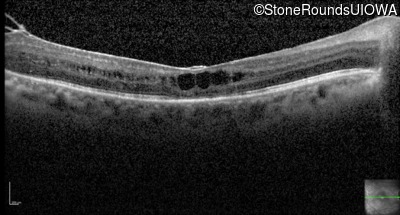

Optical Coherence Tomography - Right - 20/50 +2

Exemplar / OCT Stack